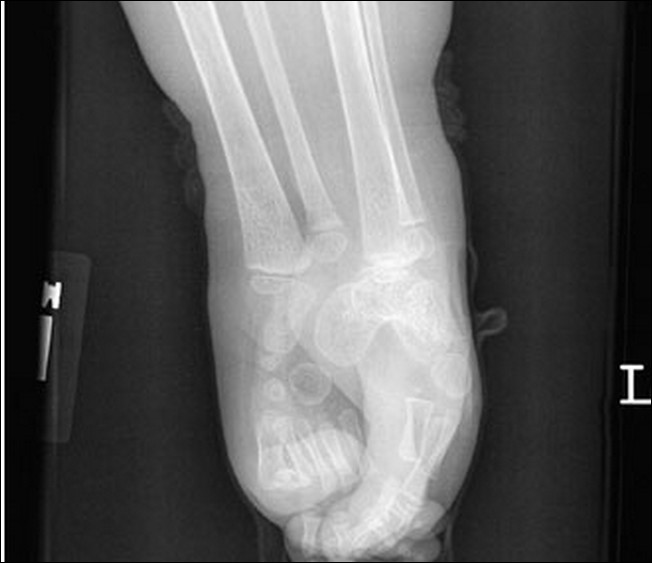

3. Mermaid Syndrome

Mermaid Syndrome yaitu bayi yang ketika lahir kedua kakinya bergabung dan menjadi satu.. seolah-olah seperti ekor putri duyung... kemungkinan terjadinya adalah satu dibanding 100.000 kelahiran... setelah satu ataupun dua hari bayi yang terkena kelainan tsb biasanya akan meninggal dikarenakan adanya komplikasi di kandung kemih dan ginjalnya...